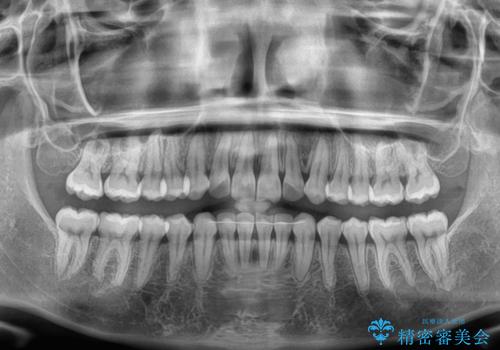

前歯のデコボコをインビザライン矯正で綺麗に改善

- 上下前歯のデコボコを気にして来院された患者様です。

全体的に叢生は軽度であったため、インビザラインにて矯正治療を行うこととしました。